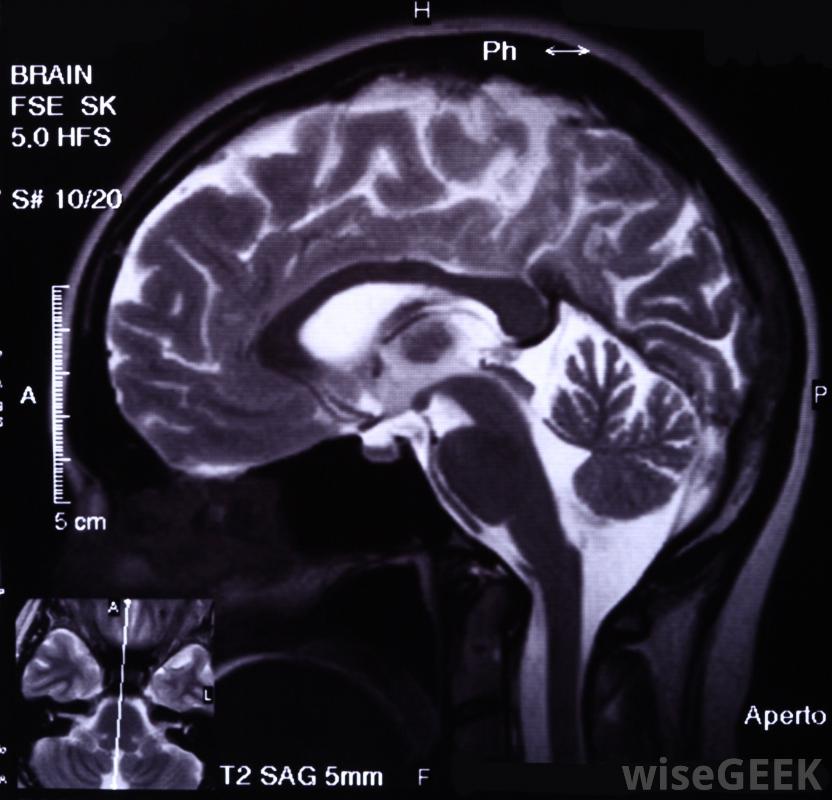

非典型脑膜瘤患者可能会出现头痛。这是最常见的脑瘤之一,脑膜瘤约占所有此类癌症的30%。脑膜瘤的诊断通常是通过磁共振成像(MRI)进行的。有症状的患者将首先接受神经系统检查,然后进行脑部成像,以确定是否患有脑肿瘤。对于无症状的患者,有时会进行诊断发生在另一个医疗投诉的脑部成像过程中。

脑膜瘤肿瘤通常通过脑部成像(如MRI扫描)进行诊断有症状的病人常有非典型或恶性变异他们报告神经系统症状,如头痛、癫痫发作、感觉丧失、恶心、视力模糊和对光敏感,几乎可以在神经系统的任何地方发生,但大多数脑膜瘤发生在头部,通常靠近脑干、颅底、静脉窦或视神经鞘脑膜瘤是最常见的脑瘤之一,约占所有此类肿瘤的30%中年以上女性多见,儿童少见;男性少见脊膜瘤,其生长速度比Ⅰ级肿瘤快,但其生长速度不如明显恶性的脑膜瘤,II级脑膜瘤占总发病率不到10%,恶性II级脑膜瘤约占2%。